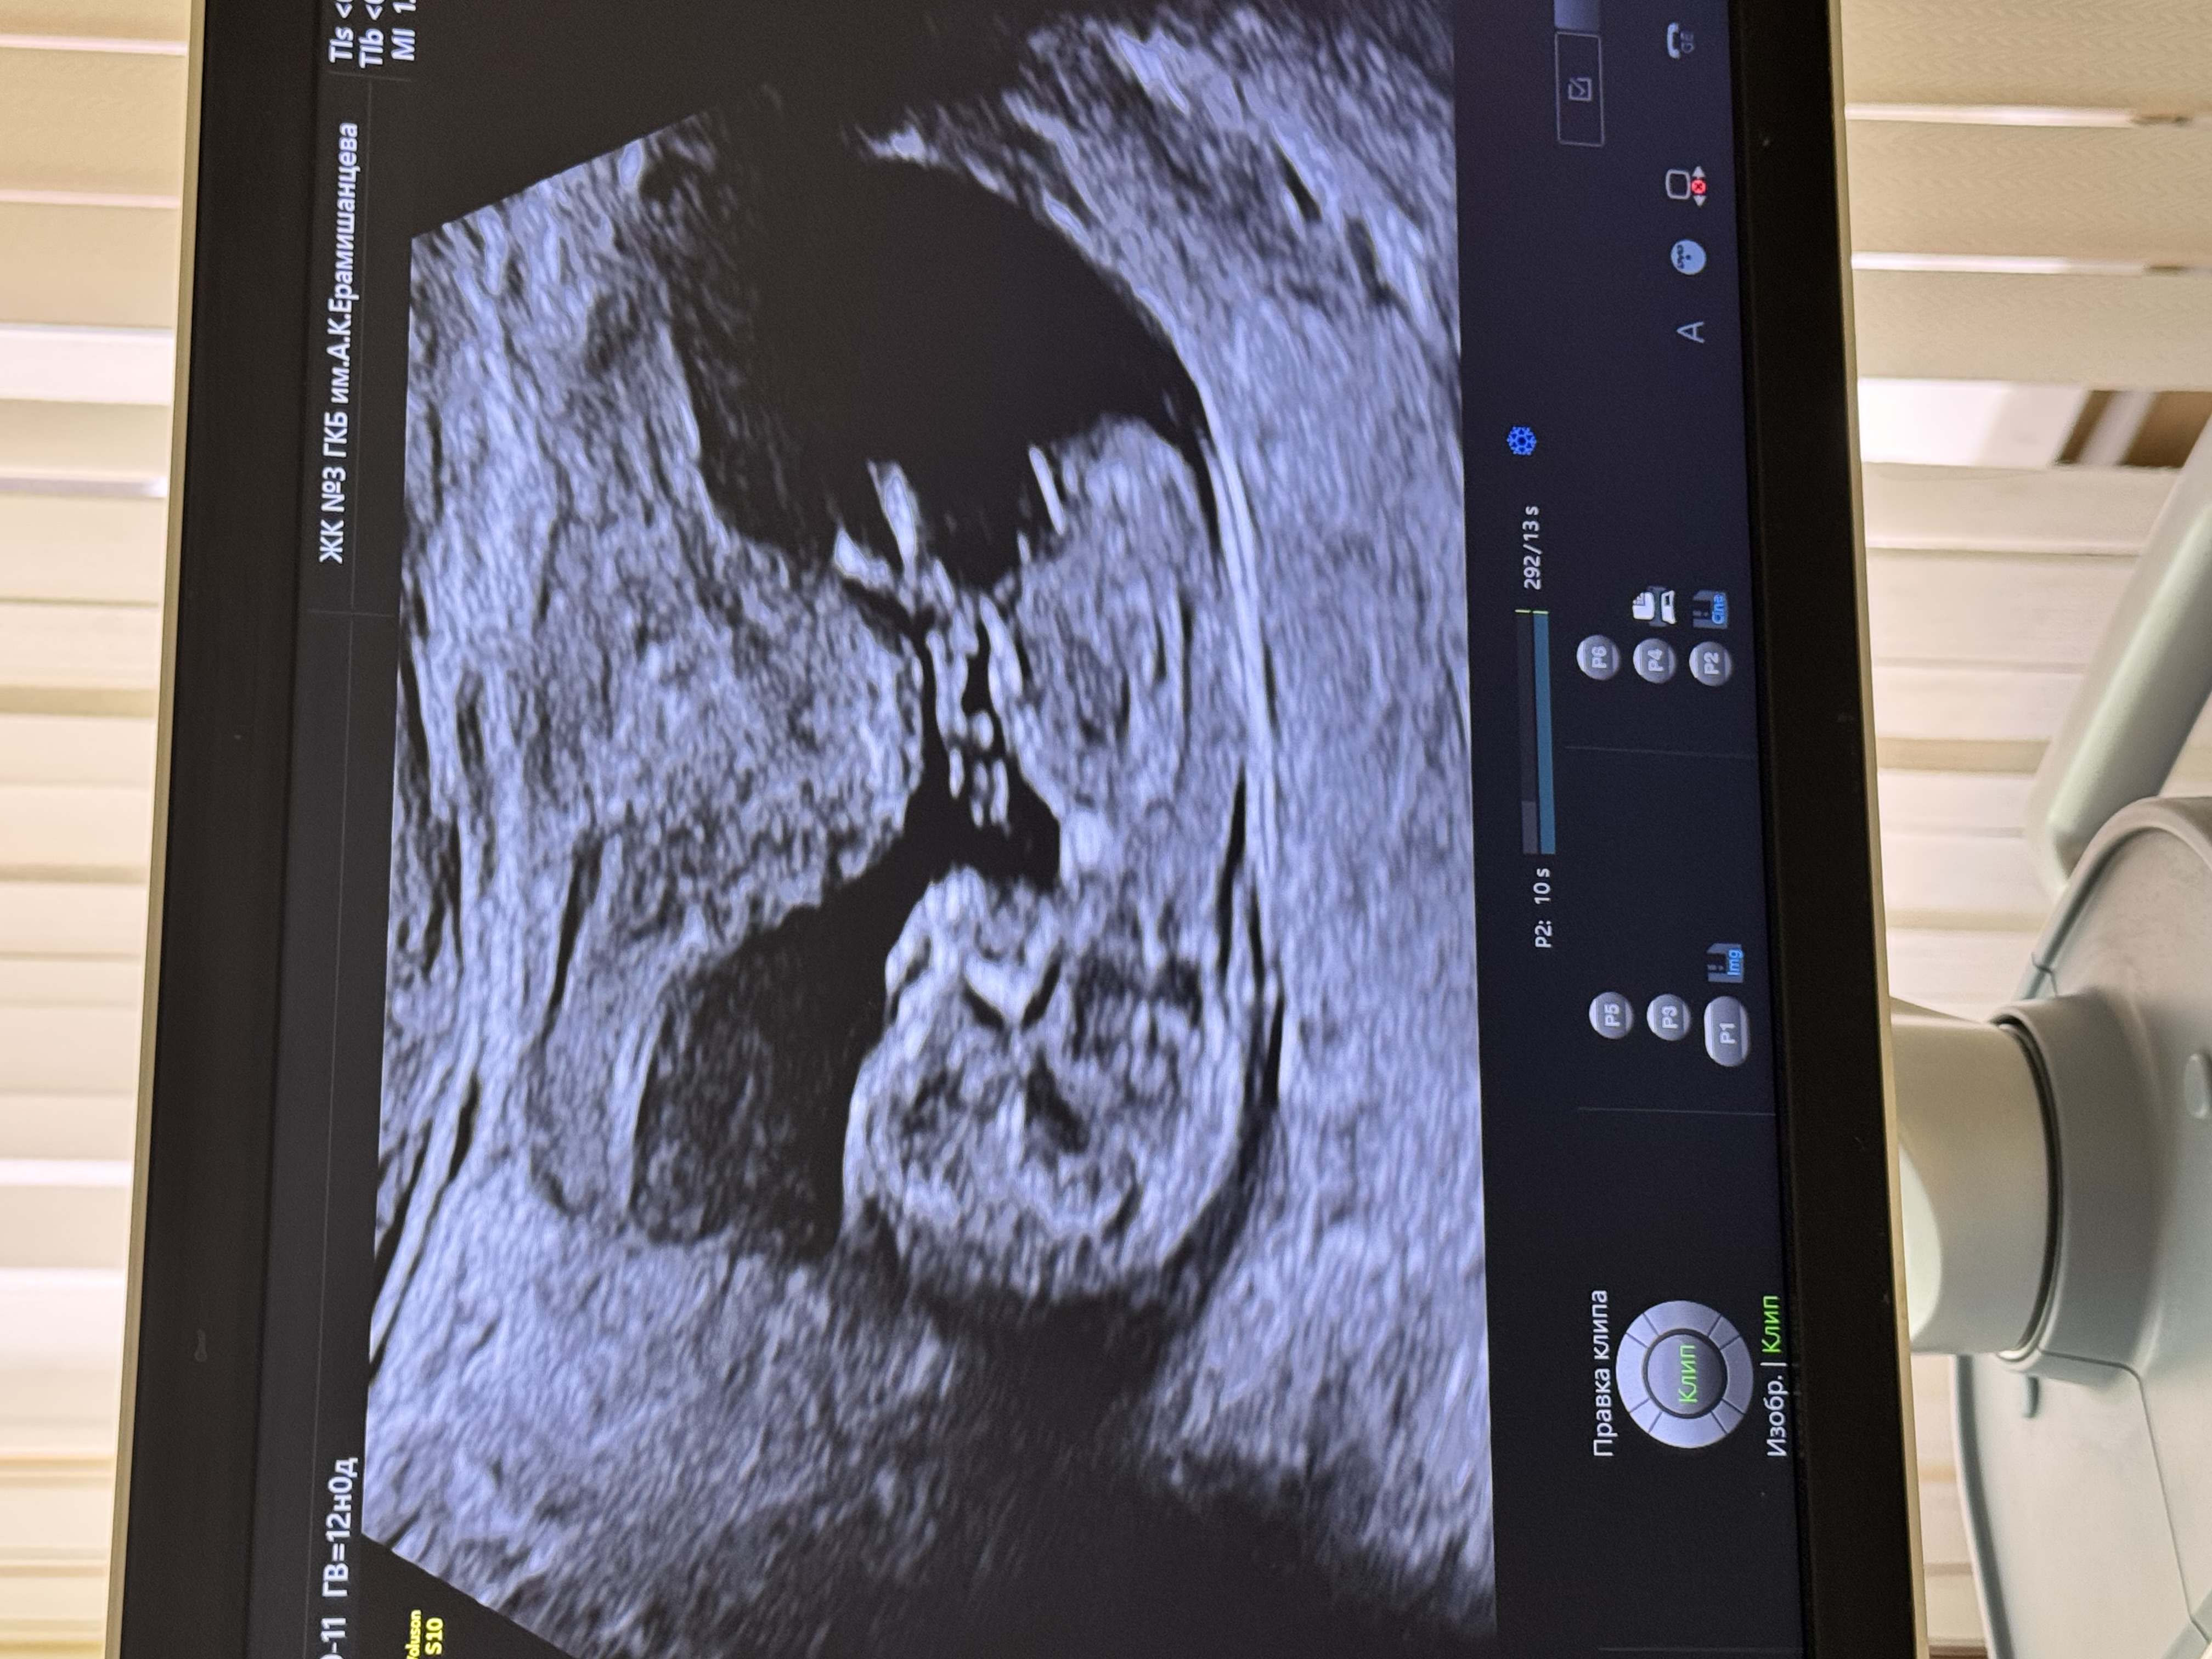

Скрининг ❤️